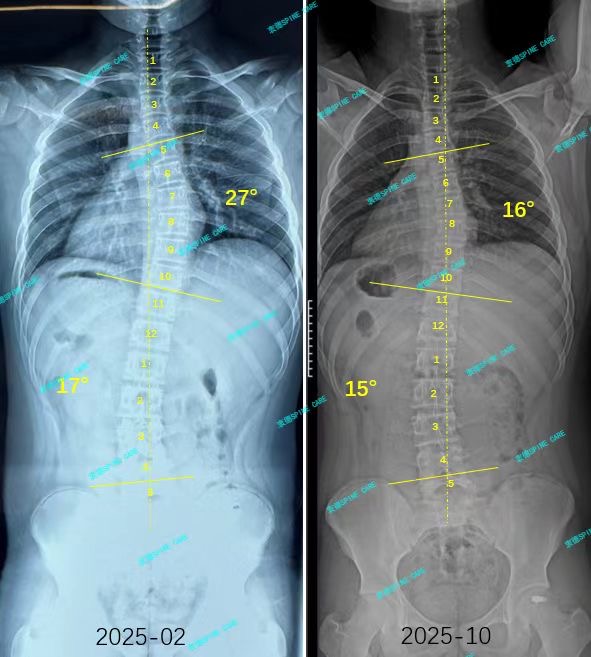

衷德脊柱,我们只关注侧弯保守治疗~

Zhongde Spine, bending no breaking ~